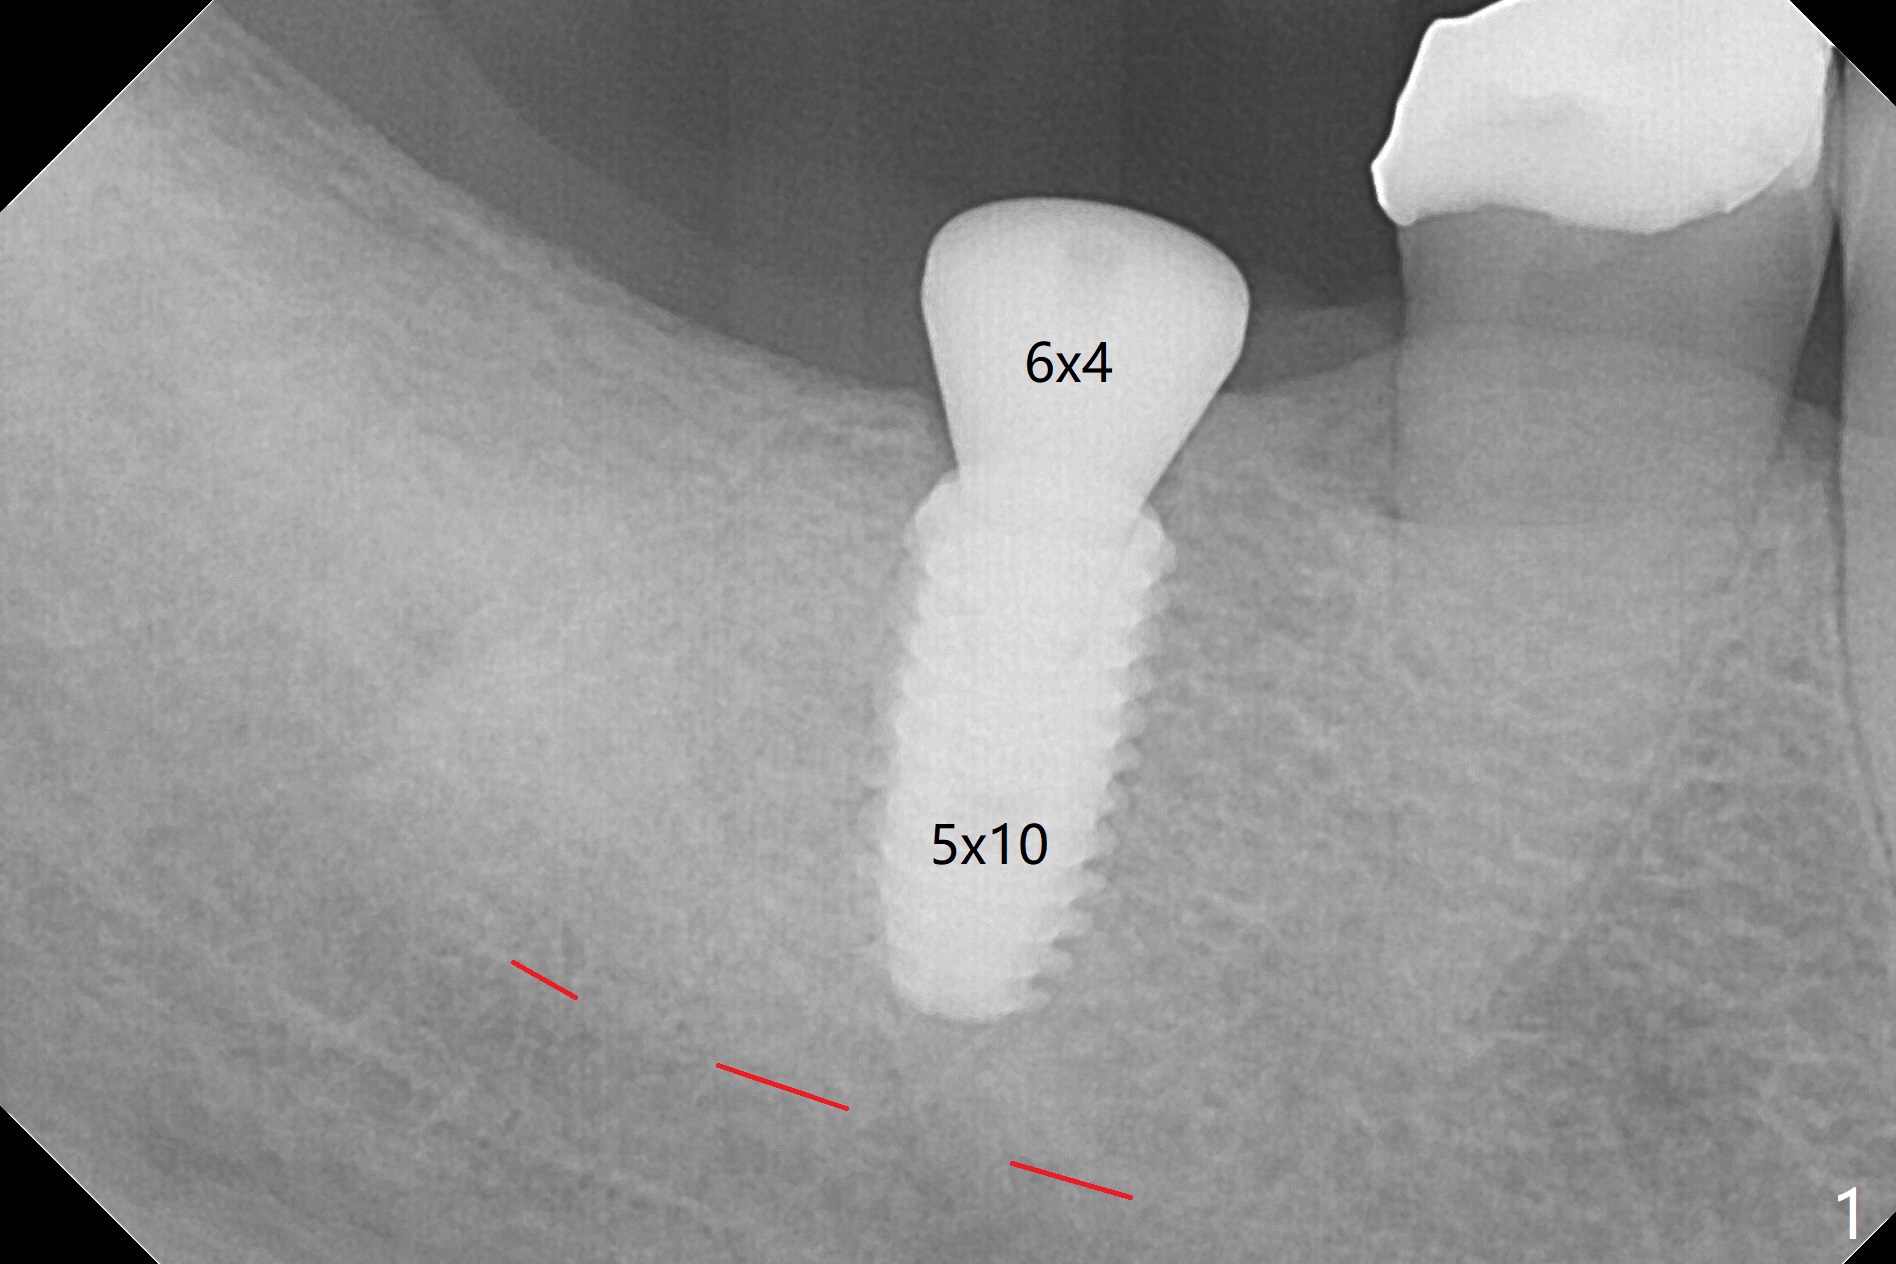

Two carpules of anesthetic is administered at #30 for the apprehensive patient, as compared to one for most cases. He is extremely pleased when the guided surgery is finished in a quick and painless manner (Fig.1). There is no bone loss 4 months postop (Fig.2); impression is taken.